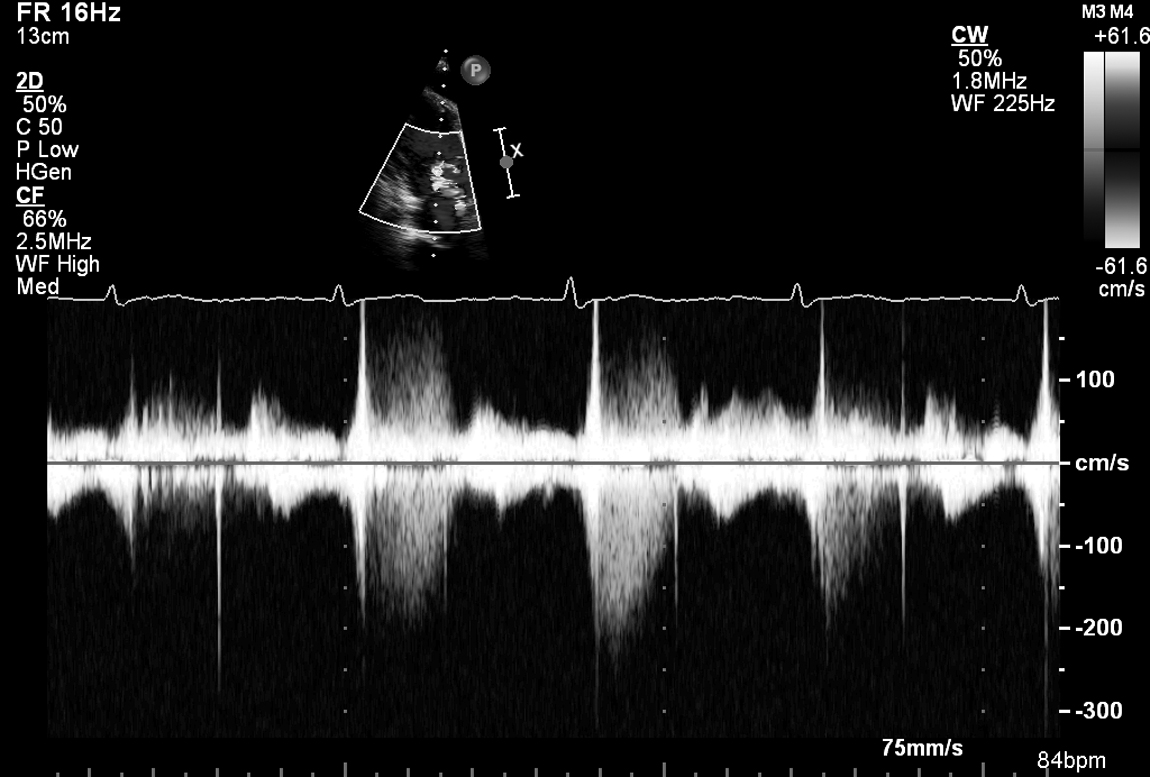

A 66-year-old woman presents with worsening exertional dyspnoea and peripheral oedema. A preliminary clinical diagnosis of heart failure is made. Her echo is shown in Figs 13.1 and 13.2 and Videos 13.1, 13.2, 13.3, 13.4, 13.5, 13.6, 13.7, 13.8, 13.9 and 13.10.

Q1. The transmitral Doppler waveform variation with breathing suggests: (Select ONE option)